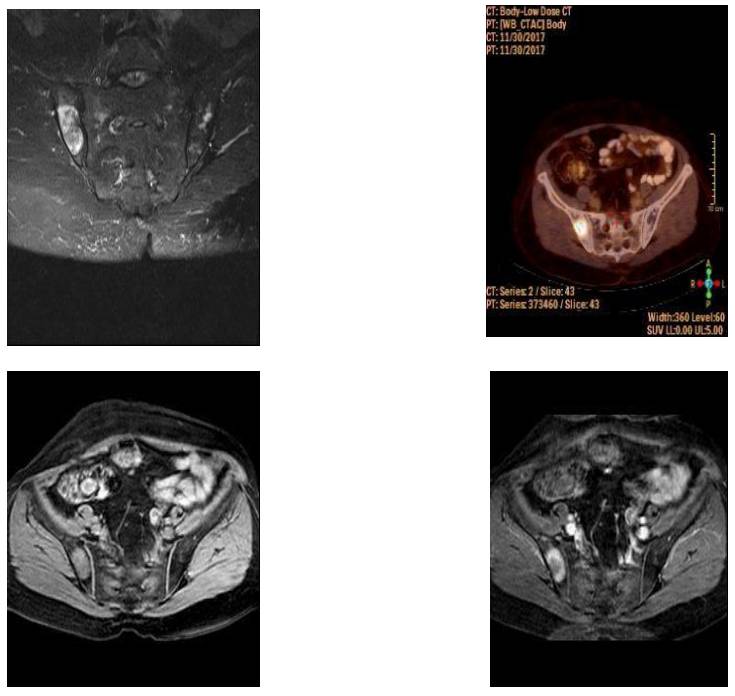

CASE 12: Sacroiliac Chondrosarcoma

- Hits: 36

- 46 year old man

- The pain and swelling in the lower back, which has been present for 5 months, has increased over time and makes it difficult to sit for long periods.

- 34-year-old woman

- The patient presented with swelling and pain in the right hip area, numbness in the right foot, and difficulty walking.

- 47-year-old female patient

- She has a history of surgery and radiotherapy for cervical cancer.